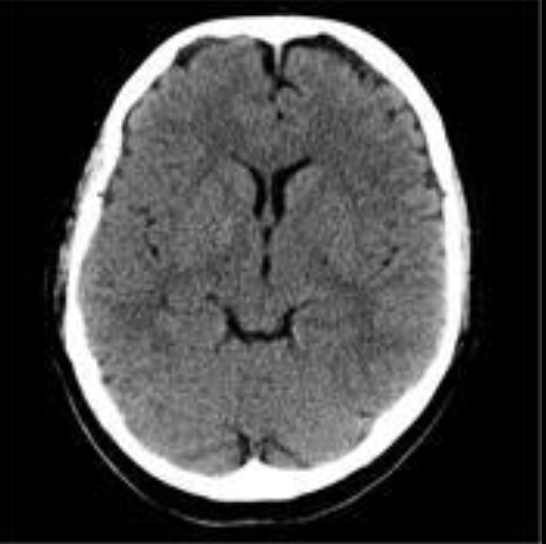

2

Q

A

EVC isquémico

Fase hiperaguda